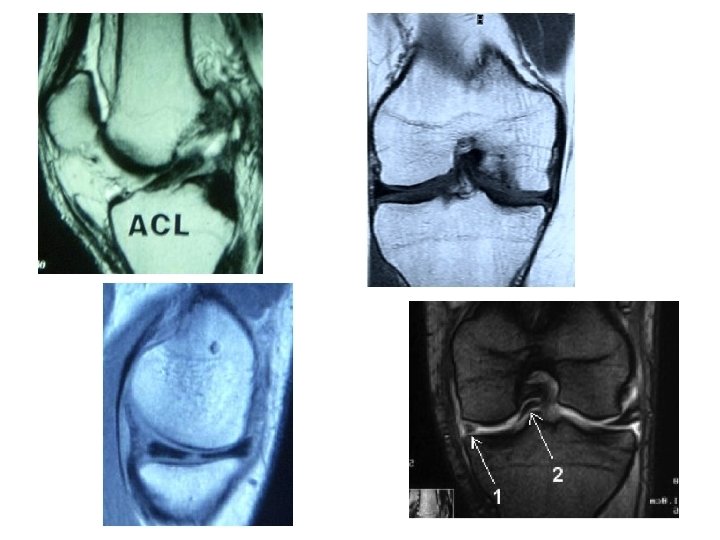

Examens complémentaires • Échographie : Non • Scanner : non sauf CID IRM; préférer l’arthro – TDM (lésion ostéo – chondrale associée) • IRM +++ – Pas trop près de l’entorse (épanchement) – Confirme la rupture du LCA – Lésions associées: • Ligamentaires • Méniscales • Ostéo - chondrales